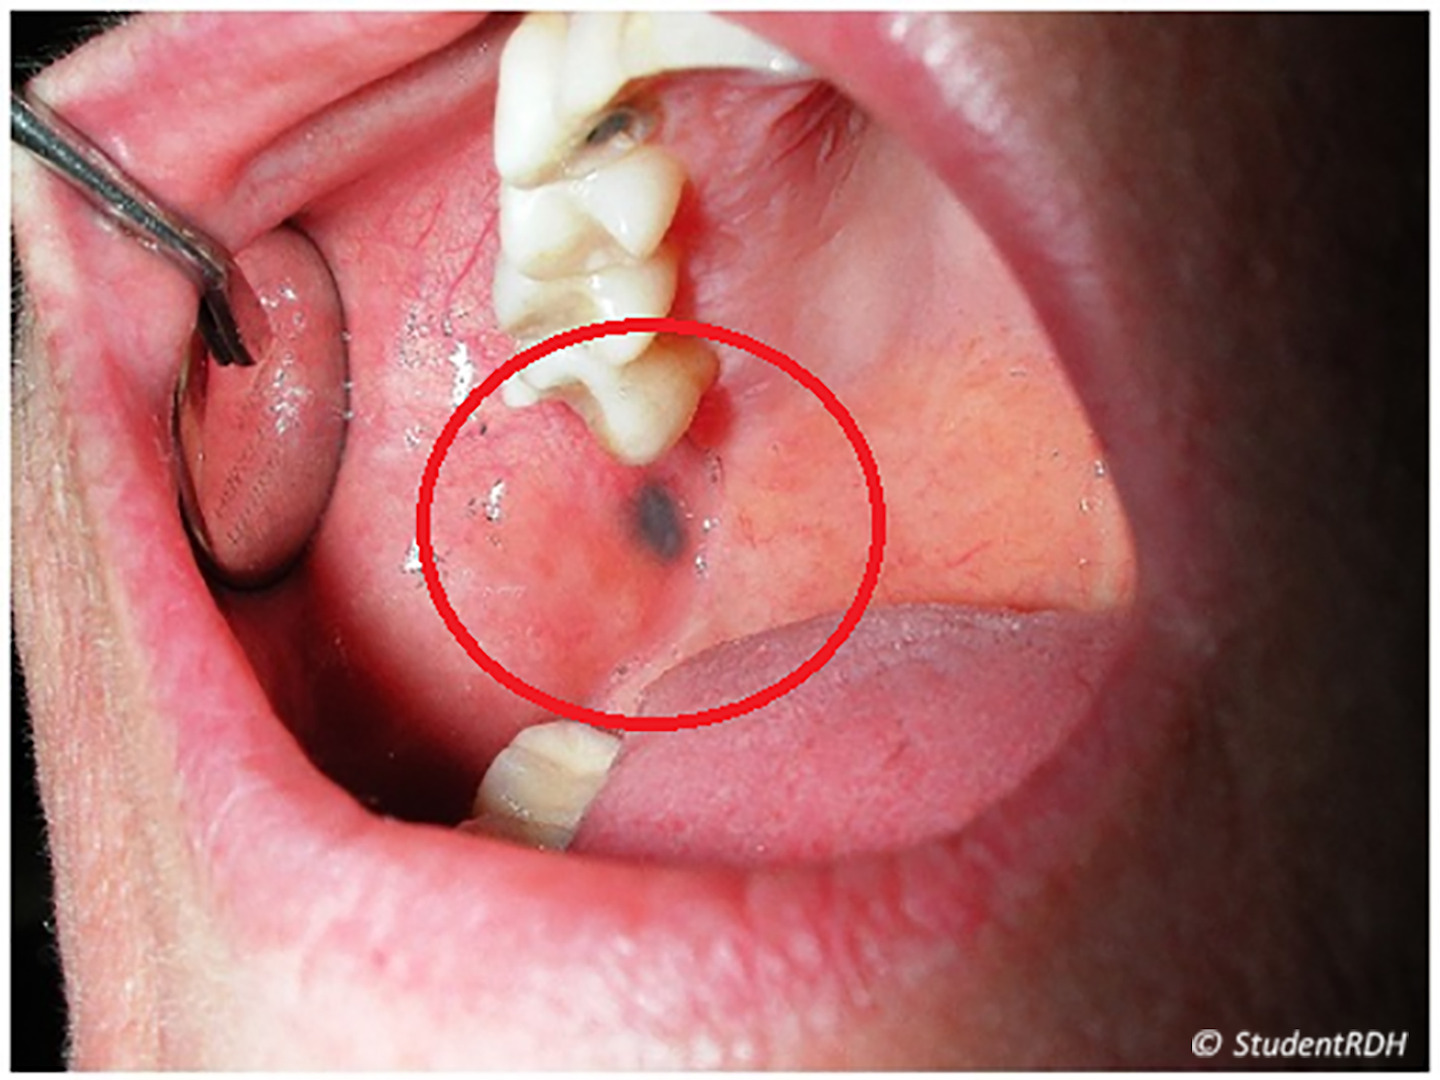

an amalgam tattoo isn’t like a rose drawn on your arm. This type of tattoo is actually a side effect of common dental. Web regarding the 458 pigmented lesions, amalgam tattoos were noted as the diagnosis of 46.3% of the specimens,. © ajr_images / adobe stock. Web amalgam tattoo is a common localized area of blue, gray, or black pigmentation.

© ajr_images / adobe stock. Amalgam tattoos are isolated pigmentations commonly found on the oral mucosa,. Web amalgam tattoo is a common localized area of blue, gray, or black pigmentation caused by amalgam that has been embedded into. an amalgam tattoo isn’t like a rose drawn on your arm. This type of tattoo is actually a side effect of common.